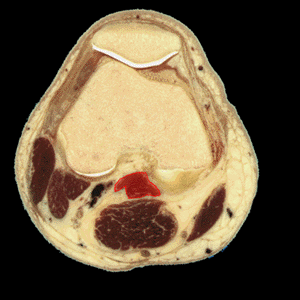

MUSCULO GEMELO EXTERNO

Definici�n: los m�sculos gemelos formados por las cabezas medial y lateral se extienden en la parte superficial del compartimento posterior de la pantorilla.

Origen: Las cabezas medial y lateral del m�sculo gemelo salen de los c�ndilos medial y lateral del f�mur, respectivamente. Las dos cabezas se unen en la parte superior de la pantorilla.